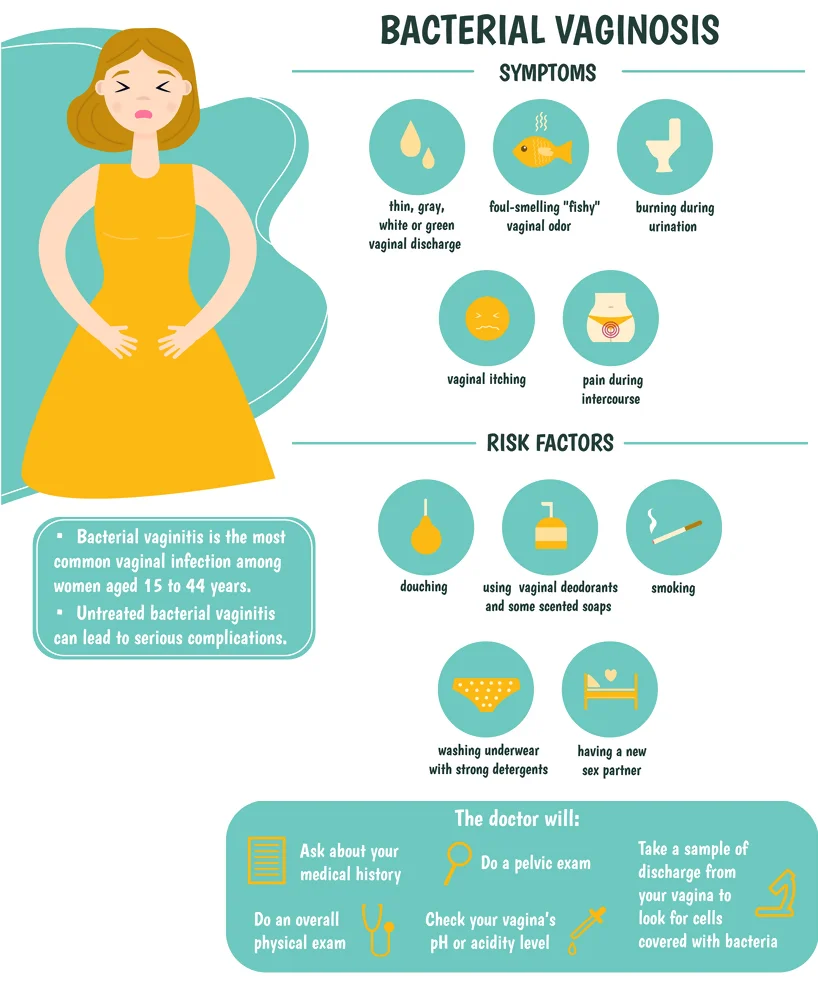

Bacterial Vaginosis Treatment:

Bacterial vaginosis (BV), also known as yeast or Candidiasis, is a sexually transmitted infection (STI) that most commonly affects women. The infection is caused by the bacterium Gardnerella vaginalis, which is present in the vagina of nearly half of all women. BV can cause odor, discharge, itching, and pain during sexual activity. BV is usually a mild, self-limited condition that can be treated with antibiotics if it becomes severe. However, BV can increase your risk of other health problems, so it’s important to get it checked out if you think you might have it.